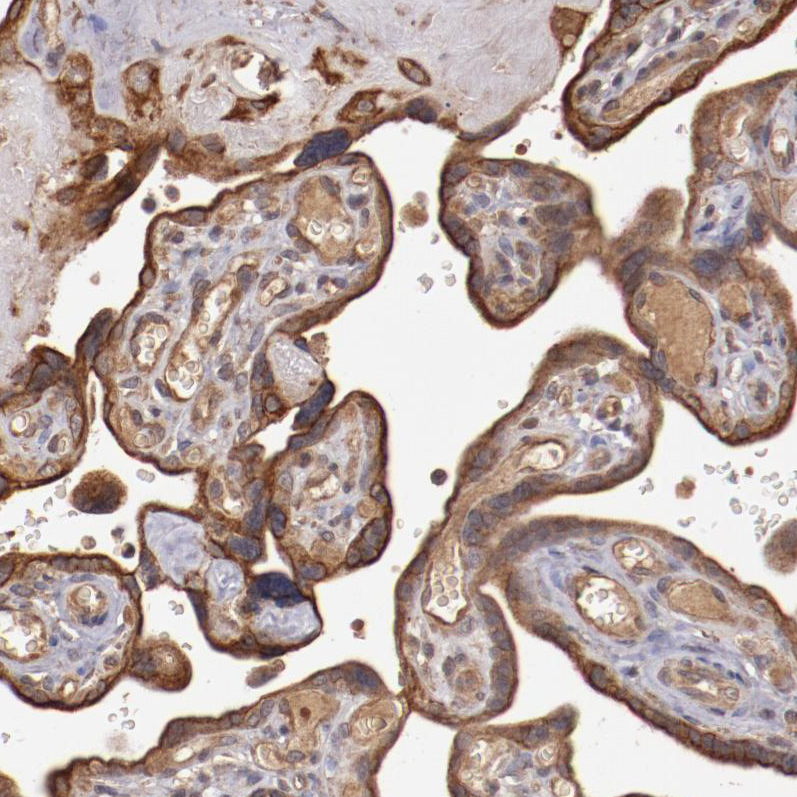

Immunohistochemical staining of human lung shows moderate cytoplasmic positivity in pneumocytes and alveolar macrophages.